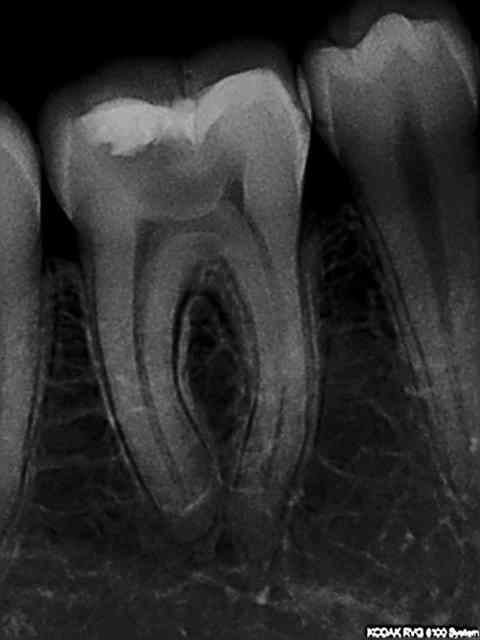

Radio initiale, cone en place , cone scellé, radio du bouchon apical réalisé au système b, puis radio finale après thermo-condensation. C'est obligatoire avec la nouvelle CCAM. Fini de jouer au dentiste le 1er juin.)))))))

Elles sont dans le désordre , remets les en ordre ( ca fait partie d'un qcm de formation continue) vu que le niveau de la formation initiale semble resté bloqué dans les années 80.